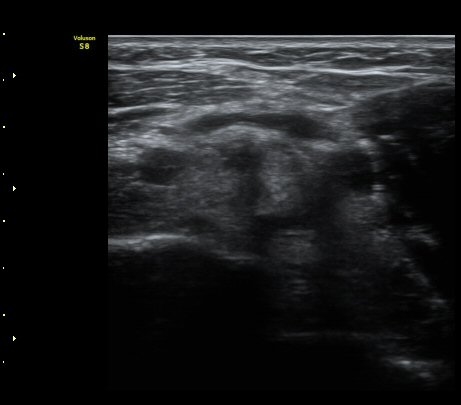

ÆÈ²ÞÄ¡ ¾Õ Ⱦ´Ü¸é°Ë»ç¿¡¼­ À̵ιڱÙÀÌ ÈûÁÙ·Î ÀÌÇàµÇ´Â °ÍÀÌ °üÂûµÈ´Ù(±×¸² 1, 2).

ŽÃËÀÚ¸¦ Á¶±Ý ¸»´ÜÀ¸·Î À̵¿ÇÏ´Ï À̵ιڱ٠ÈûÁÙÀÌ ¶Ñ·ÈÇÏ°Ô °üÂûµÇ°í ÇÔÁÙ ÁÖÀ§¿¡

¼ö¾×Àú·ù°¡  º¸ÀδÙ(±×¸² 3, 4, 5, 6)